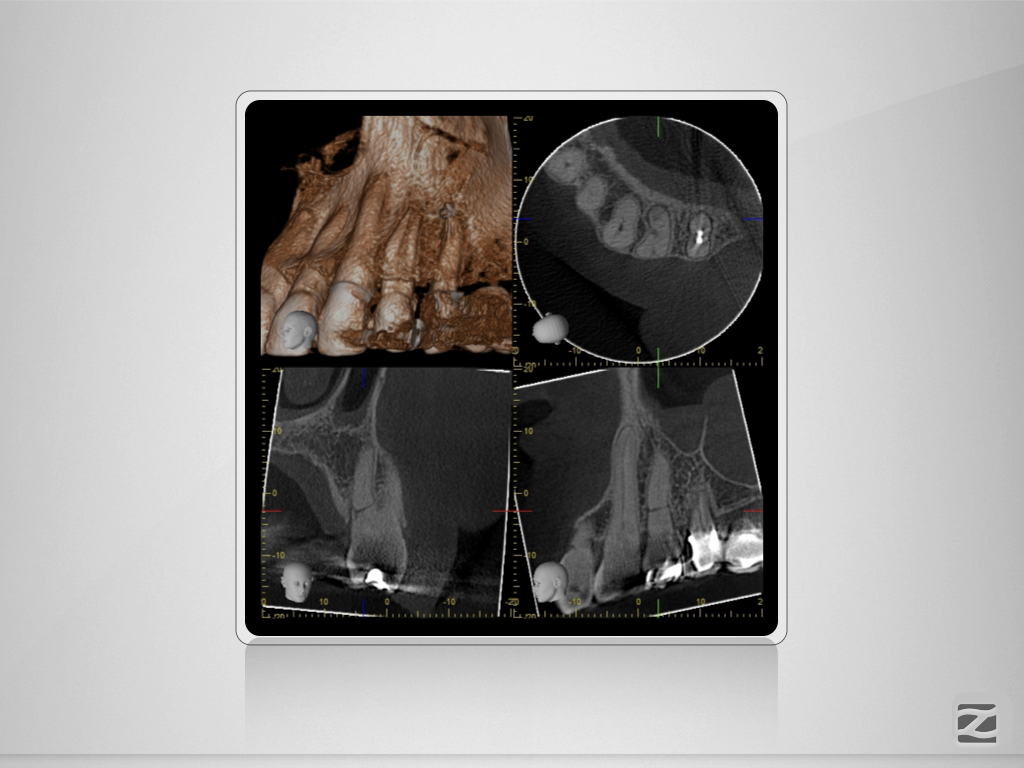

24D.003

Und nun? Die Auflösung.